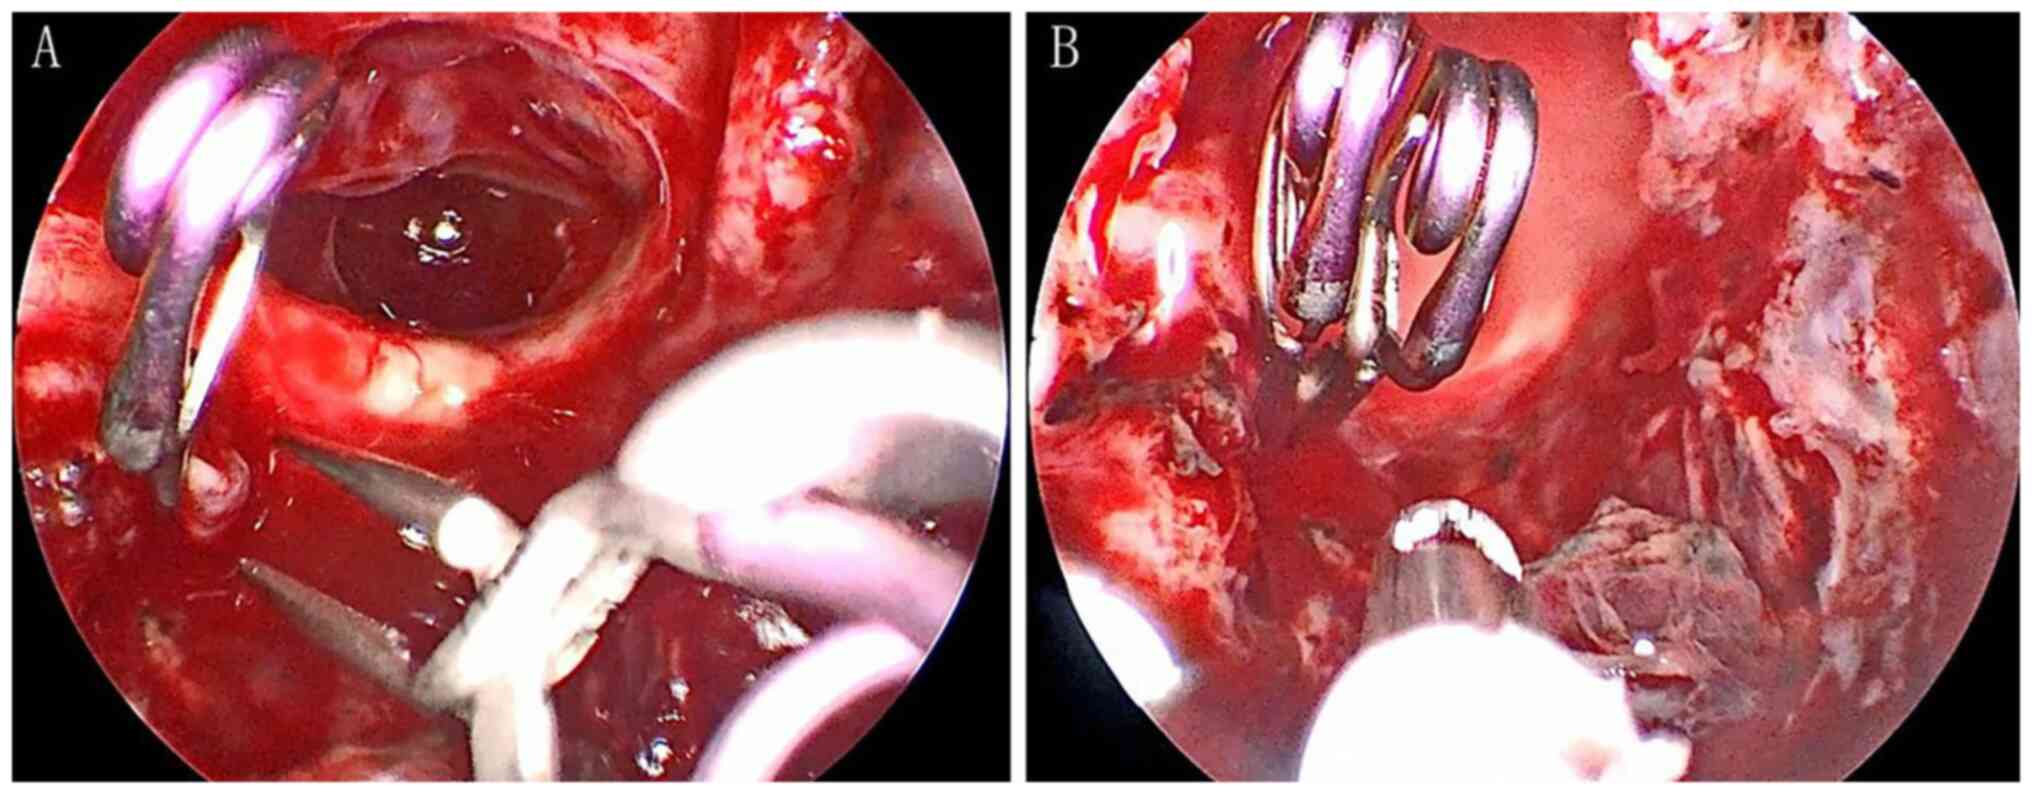

Craniopharyngioma resection and aneurysm clipping performed simultaneously by pure endoscopic endonasal approach: A case report and literature review

Craniopharyngioma is one of the most challenging issues for neurosurgeons as a brain tumor. Among the approaches of neurosurgery, in comparison to craniotomy, the endoscopic endonasal approach (EEA) has risen in popularity over the last two decades; unruptured intracranial aneurysms are relatively commonly found in the general population. The EEA as a new paradigm in the treatment of aneurysm has been reported to successfully clip dozens of cases of intracranial aneurysm. However, when reviewing the domestic and foreign literature, it appeared that cases of craniopharyngioma complicated with intracranial aneurysm purely treated by EEA have not been reported so far. In the present study, the published literature regarding endoscopic endonasal surgery for craniopharyngioma and intracranial aneurysms was reviewed, accompanied with a case of craniopharyngioma complicated with intracranial aneurysm, both of which were simultaneously treated by EEA.